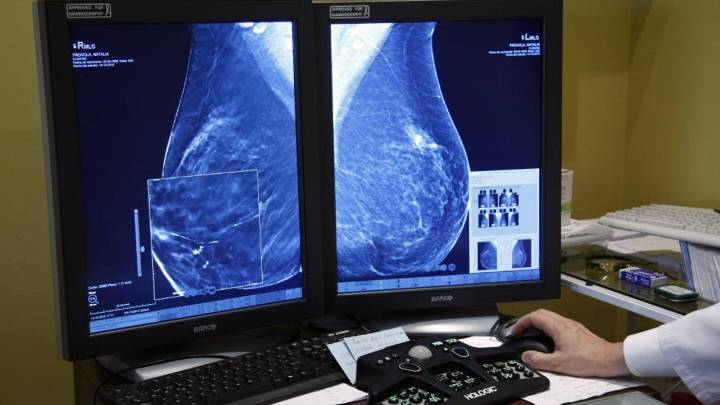

La portavoz de la comisión de participación y seguimiento del plan de acción del cribado de cáncer de mama y coordinadora de los referentes de unidad de mama hospitalaria de Andalucía, Mercedes Acebal, ha aclarado este sábado que la empresa contratada para el mantenimiento técnico del programa del cribado del cáncer de mama "no hace ningún seguimiento de casos".

"Es más: no usa si quiera la herramienta y su labor se limita exclusivamente a mantenerla operativa y en funcionamiento para que puedan manejarla los usuarios, que son los responsables de los centros y los profesionales". Así lo ha explicado Mercedes Acebal en un vídeo remitido a los medios por la Junta de Andalucía.

De esta forma, la Junta sale al paso de lo publicado este sábado por 'El País'. En su información, se explica que